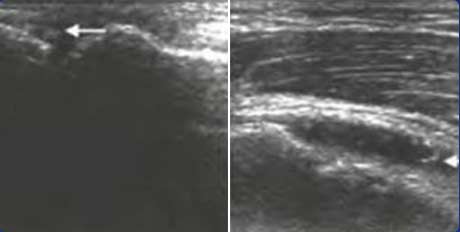

二、清晰显示软骨表面尿酸盐结晶沉积状况 判断痛风所属病期

肌骨超声可通过高清影像图判定软骨表面有无出现一条与强回声骨皮质平行的线样强回声,即“双轨征”这一痛风性关节炎特征性表现,判定疾病所属。当尿酸盐粘附并沉积于漂浮的滑膜上时,超声检查可在关节腔内发现漂浮的高亮回声;而当尿酸盐长期沉积于韧带上时,在超声中即显示条带状的略高回声(韧带)中出现高回声点、高回声带或高回声团块(尿酸盐),从而判断痛风病情处于哪一时期。

“双轨征”

跖趾关节软骨表面可见高回声不规则增强的软骨滑膜边缘线,呈“双轨征”。

高回声带

软骨表面回声增强,与深面的骨性关节面强回声线形成“双轨征”。

聚集体

髁软骨的双轨征状,显示髌腱内部的聚集体